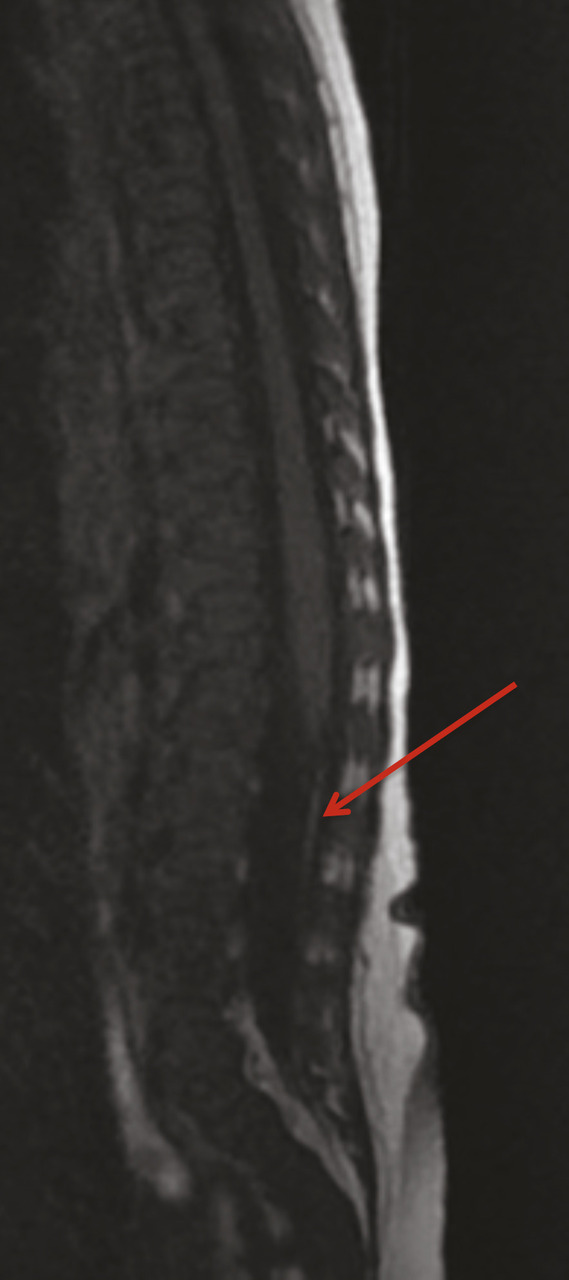

Les filums lipomateux (fig. 2 ) peuvent être découverts plus tardivement, l’incontinence urinaire en est un symptôme possible. La malformation médullaire est confirmée par une imagerie par résonance magnétique (IRM), la moelle peut se terminer sous le plateau inférieur de L2 (moelle dite basse et attachée). En cas de symptôme associé (constipation, atteinte orthopédique des membres inférieurs), les recommandations sont de sectionner chirurgicalement ce filum.8

Les filums lipomateux (